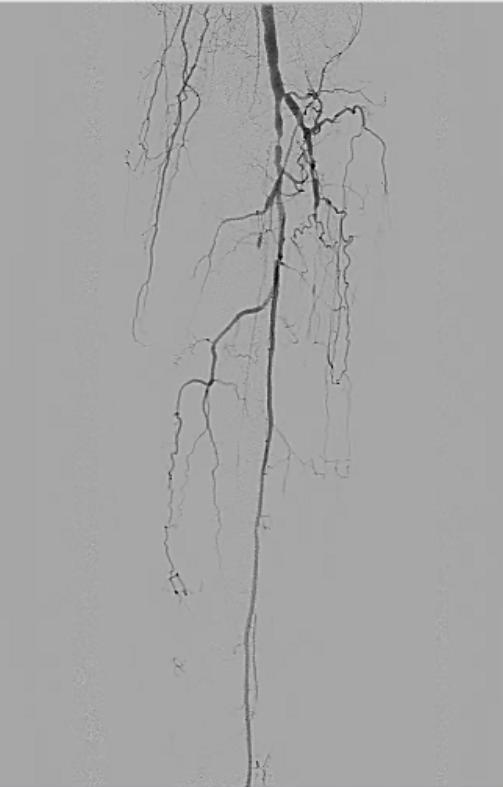

Angiography revealed bilateral occlusions of the anterior and posterior tibial arteries. Iliac and femoral arteries were free of significant disease (Figure 1):